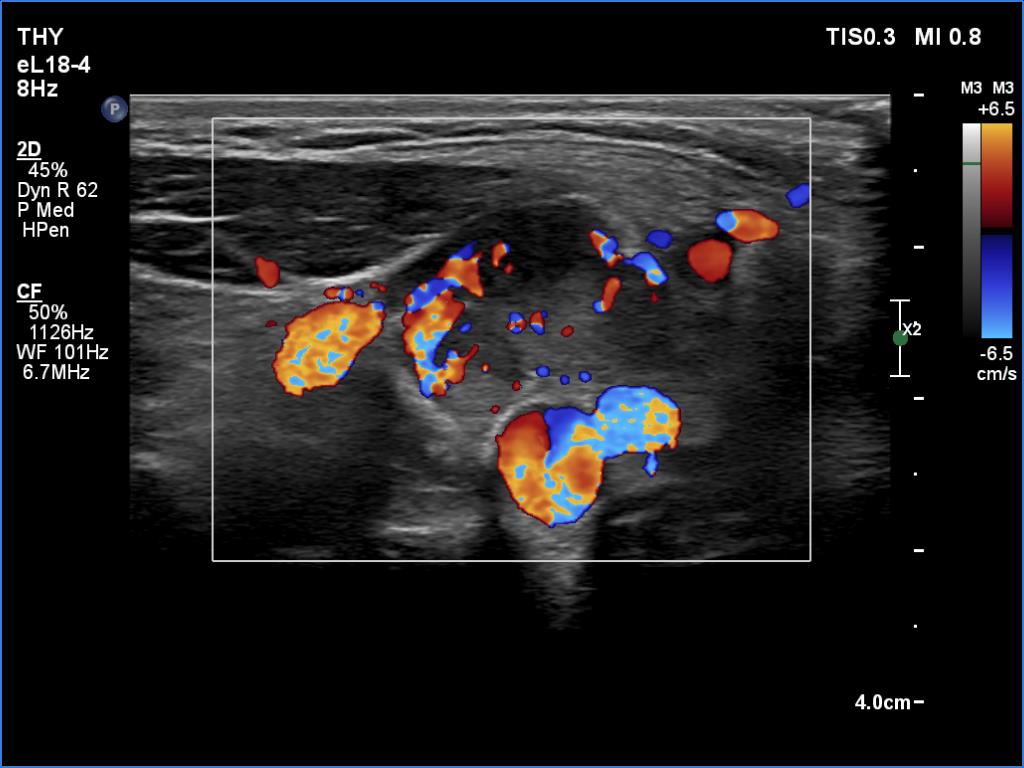

According to the palpable mass in the right submandibular area, there was a heterogeneous lesion which has hypoechoic and echonormal parts. The mass had irregular margins and showed vascularity. The distance between the submandibular mass and the thyroid was more than 35 mm.